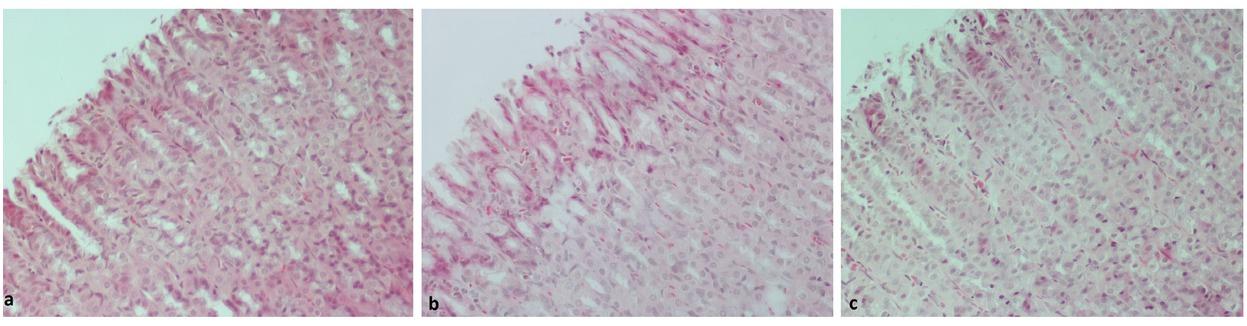

Mucosal lesions observed in the ascending colon in the three groups